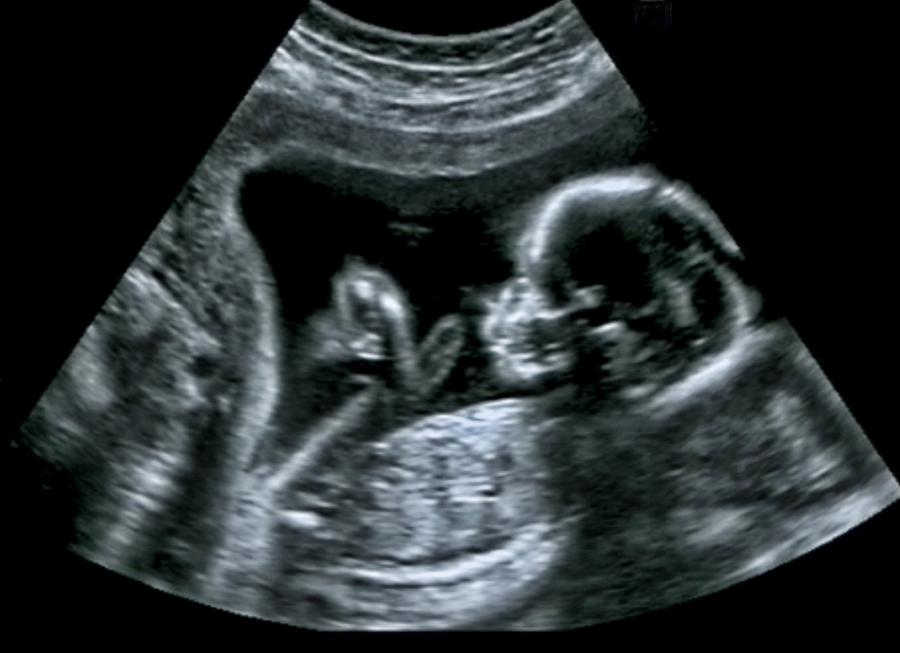

Ултразвукови изображения на плода. Долу вдясно можете да видите как плодът е направи физиономия, наподобяваща плач. Източник: Reissland et al., PLOS One, 2011

Ултразвуковите технологии ни позволяват да надникнем в матката и да наблюдаваме развитието на плода. Така например видео, публикувано през 2005 г. в Archives of Disease in Childhood – Fetal and Neonatal Edition, показва, че 33-седмичен зародиш прави лицеви изражения, които на ултразвуковия профил приличат на плач.

Екипът на Рейссланд анализира развитието на лицевите изражения в утробата, като наблюдава движенията на плода във втория и третия триместър посредством 4D ултразвук (това сканиране показва движещи се 3D снимки на бебето).